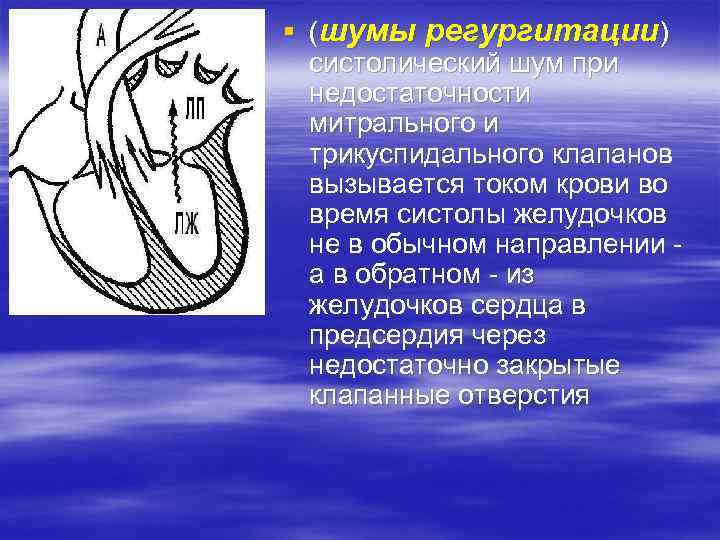

§ (шумы регургитации) систолический шум при недостаточности митрального и трикуспидального клапанов вызывается током крови во время систолы желудочков не в обычном направлении а в обратном - из желудочков сердца в предсердия через недостаточно закрытые клапанные отверстия

§ (шумы регургитации) систолический шум при недостаточности митрального и трикуспидального клапанов вызывается током крови во время систолы желудочков не в обычном направлении а в обратном - из желудочков сердца в предсердия через недостаточно закрытые клапанные отверстия